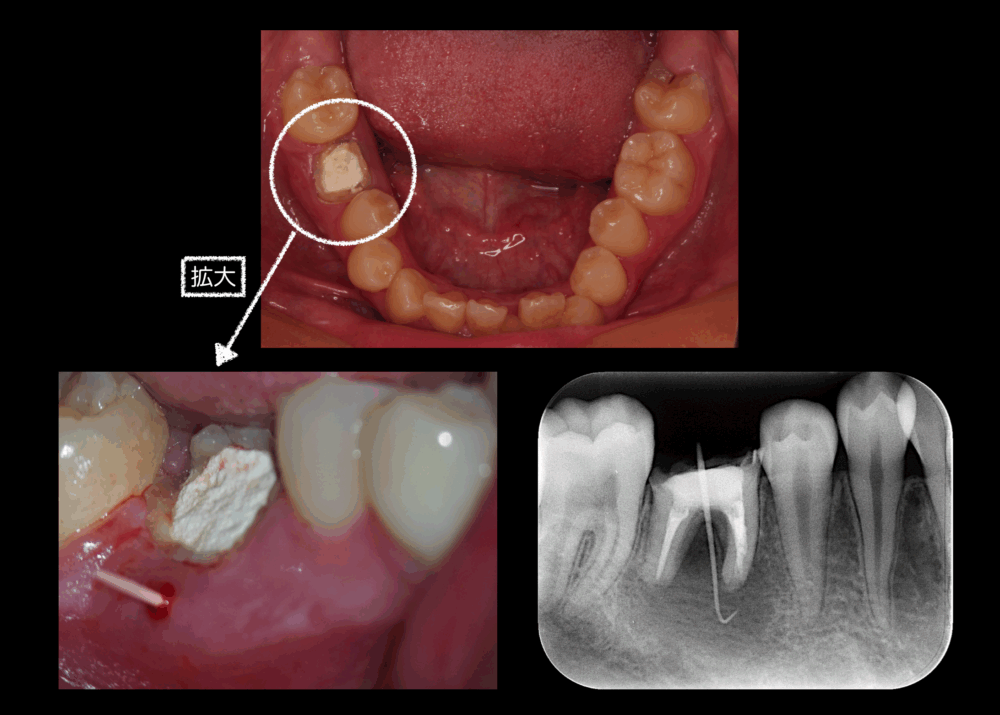

根管治療ではなく抜歯を選んだ17歳男性

ももこ歯科のブログを読んでくださる皆さま、いつもありがとうございます。 なかなかセンセーショナルなタイトルですが、事実です。将来があるからこそ、抜歯を選択されました。ちなみに、保護者同伴でももこ歯科を受診していただいてま...

どう思う?根管にある折れたファイルを取るべきか?

大変ご無沙汰しております。 新しいブログをなかなかアップできなくて、申し訳ないです。 今回は、根管にある折れたファイルを取るべきか、私の考えをお話しします。 結論から話すと、折れたファイルを取った方が根管をより消毒できる...